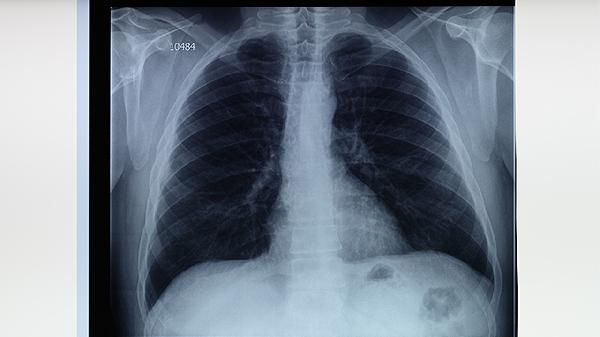

影像学检查:胸部X线或CT检查是诊断肺结核的重要手段。菌阴性肺结核的影像学表现通常为肺部浸润性病变、空洞、纤维化或钙化灶。CT检查能更清晰地显示病变的细节,有助于与其他肺部疾病如肺炎、肺癌进行鉴别。